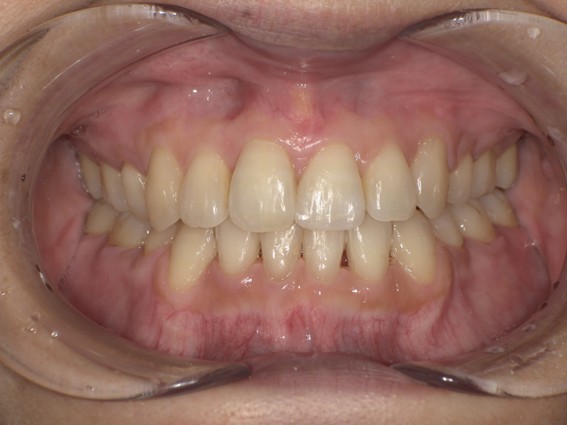

| 主訴 | 口元がでている、口が閉じずらい、上の歯と下の歯のがたつき、顎がない。 |

| 治療内容 | 上下のワイヤー矯正を行いました。 |

| 治療費 | 880,000円(税込) |

| 治療期間 | 28ヶ月 |

| 治療回数 | 28回 |

| 想定されたリスク | 知覚過敏・咬合痛・歯肉退縮・歯髄壊死・歯髄充血のリスクがありました。 |

以前骨切りを勧められたことがあるという方でしたが、抜歯矯正で口元の突出や顎のしわを改善しました。上唇の厚みや頬の高さを考慮し、老けた印象にならないよう配慮。お顔全体のバランスと年齢に合わせた治療を行いました。